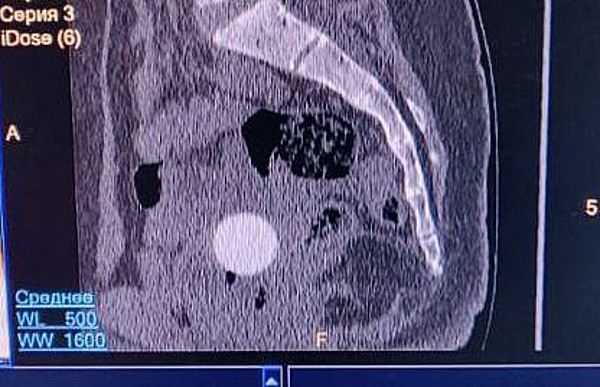

Врачи детской областной больницы удалили редкий инородный предмет из организма юной пациентки